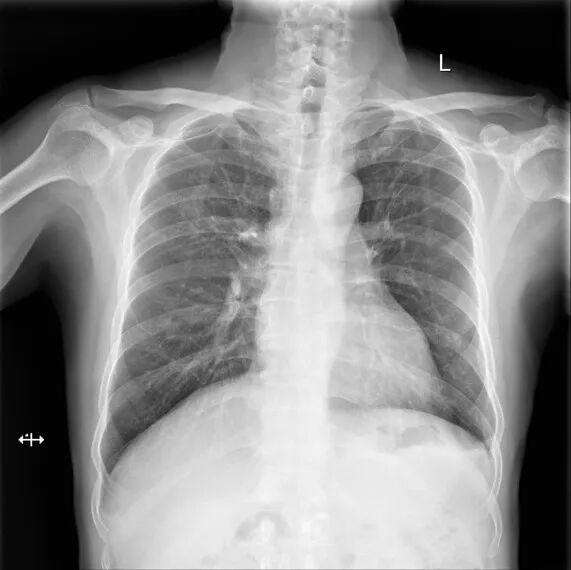

胸片

生命体征:体温:36.0℃、脉搏:73次/分、呼吸:21次/分、血压:118/82mmHg。

双肺呼吸音清,未闻及干湿啰音。

心界无扩大,心率73次/分,律齐,各瓣膜听诊区心音正常,未闻及杂音,未闻及心包摩擦音。